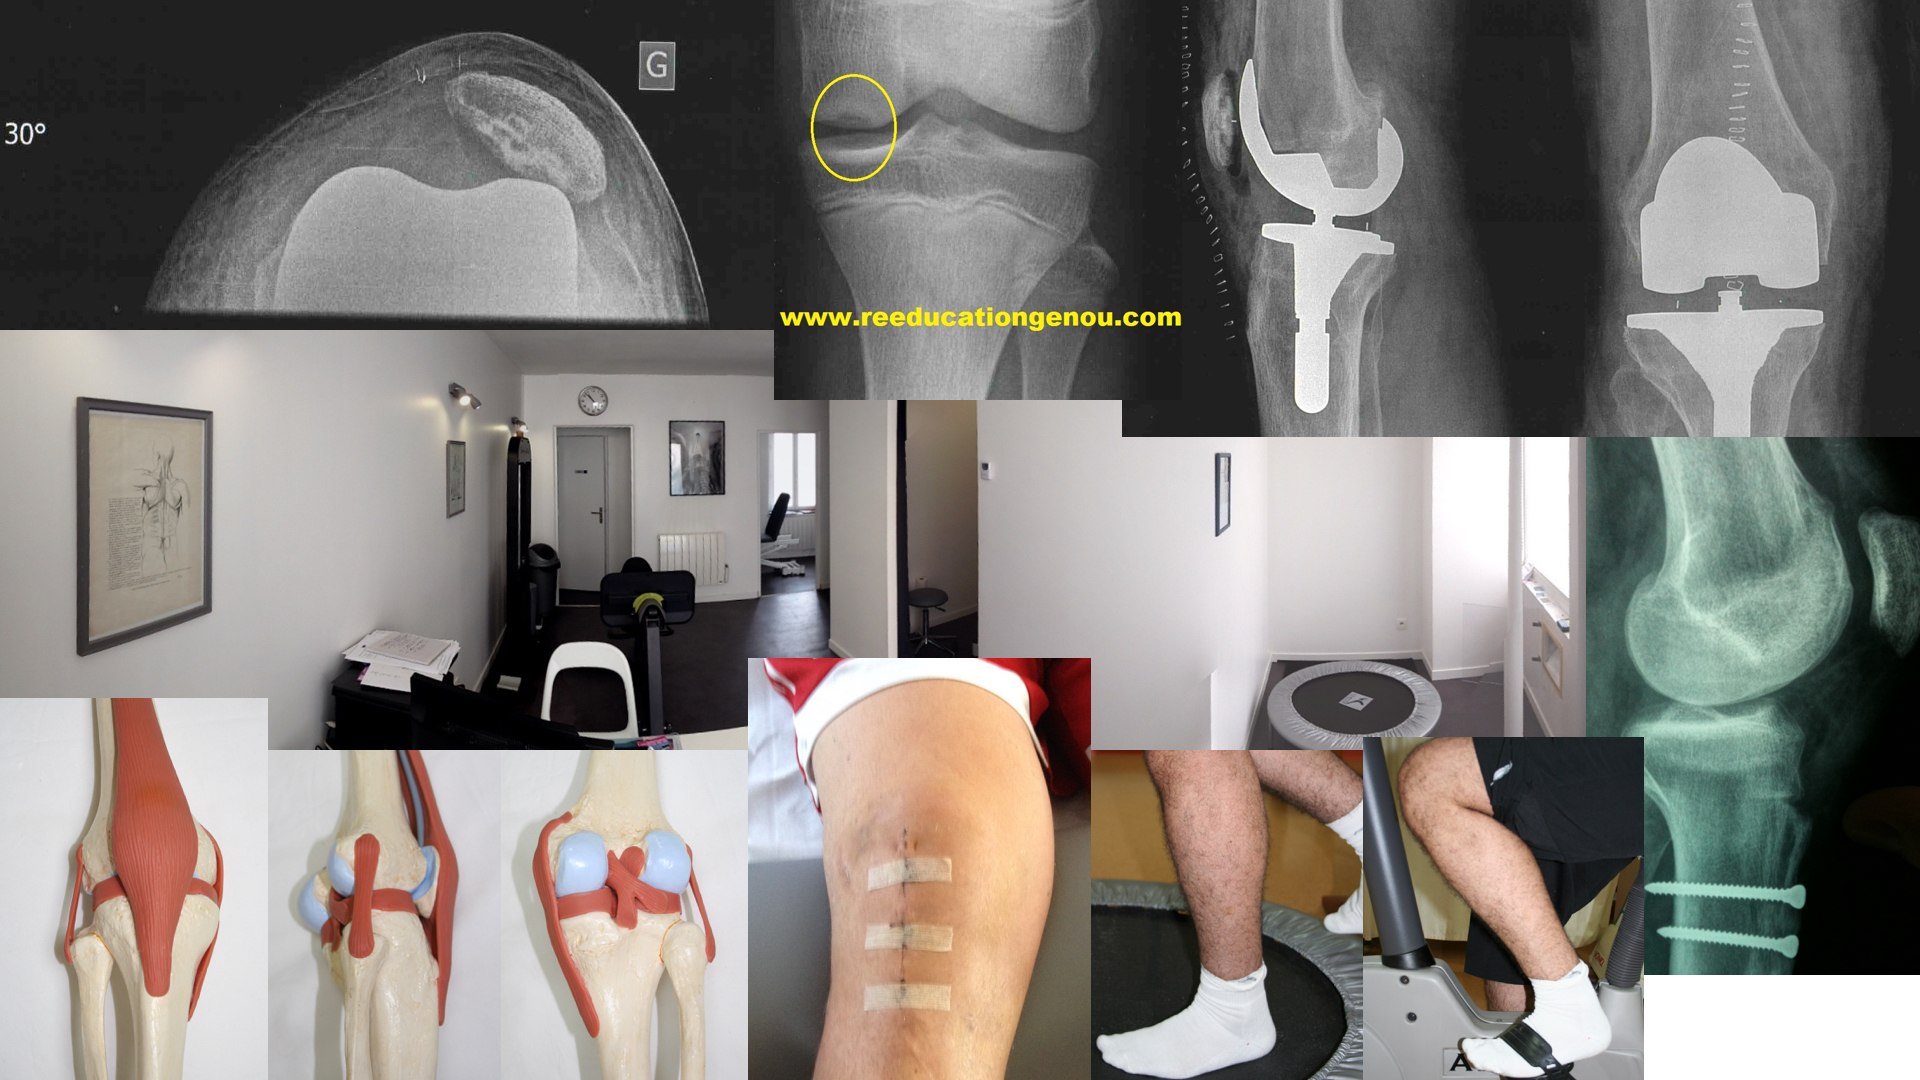

La mise en place d'une prothèse du genou vient remplacer les zones d’os et de cartilage qui sont usées par des pièces artificielles ayant les mêmes formes. Ou encore si à la suite d'une entorse du genou, le diagnostic du médecin est une lésion ou rupture du ligament croisé antérieur. L’un est appelé ménisque médial, ou interne :.

Reeducationgenou Com Ligaments Lateraux